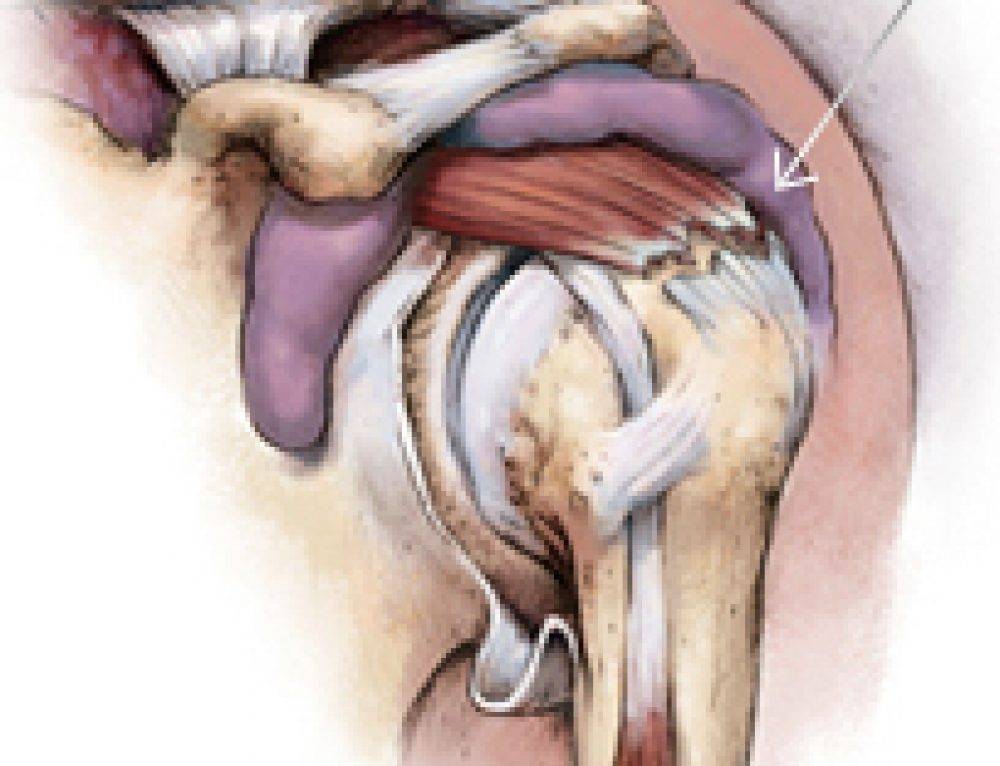

Фотографии мышц ротаторной манжеты плеча